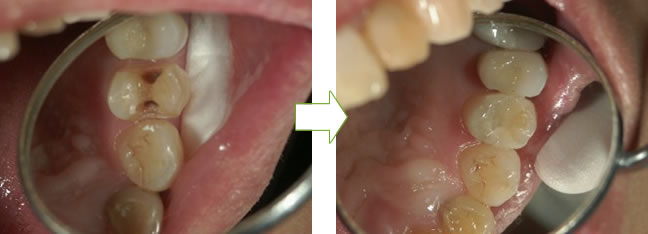

befor after

befor → ドックベストセメントを入れる → after